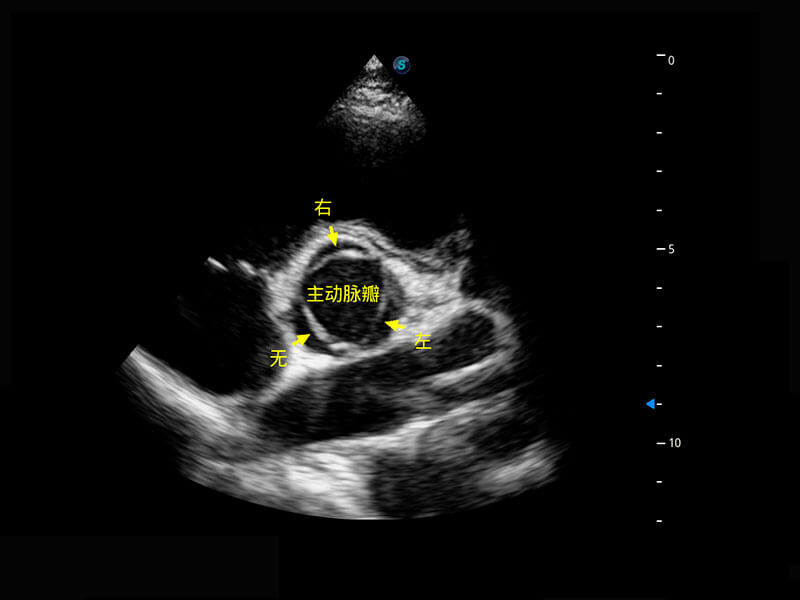

右室双出口

胎心容积成像